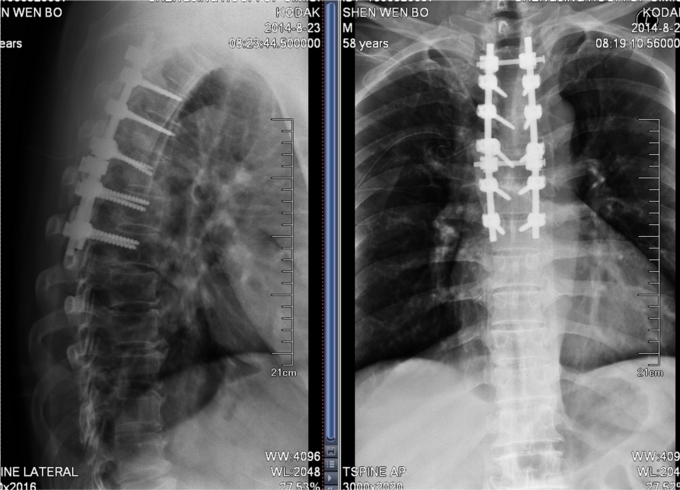

诊断:胸3-6椎体骨折,胸髓损伤,双下肢全瘫。 入院后完善检查,查无手术禁忌症后行胸椎骨折后路切开复位椎板减压椎弓根钉内固定术

患者早期手术治疗后,家属协助后可以半卧位休息,防止骨科并发症的发生,提高患者生命质量。